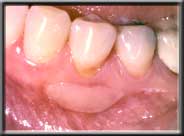

The replacement of missing attached gum is called gingival grafting. The muscle that is pulling down on the edge of the gum is first surgically resected and repositioned away from the gum margin. Then a small piece of attached gingiva is taken from the roof of the mouth, just adjacent to the back teeth, and transplanted to the site in question. The new tissue reattaches and reforms a new layer of attached gum, which should last a lifetime with proper care. The roof of the mouth heals quickly, just like a skinned knee might. With this procedure the root is not covered, and the tissue stays at the same level as before, except with attached gingiva at the margin. These procedures are very easy on the patient, and rarely require more than over-the-counter pain pills post-operatively (ibuprofen). Routine gum grafts ("gingival grafts") do not cover up the exposed root surface - if this is desired, a different technique is used (See Cosmetic Procedures, Root Coverage). Covering the root does not make the tooth stronger, for the bone, which actually holds the tooth in place, does not change regardless of the new gum level. Rather, root coverage procedures are primarily done for cosmetic reasons, or when there is exceptional root sensitivity after recession.